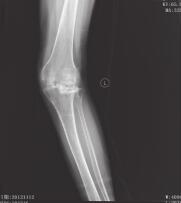

患者,女,59岁,因左膝部骨折术后畸形2年于2012年11月11日入院。约于2年前摔伤左膝部,在当地医院就诊,经X线检查,诊断为“左胫骨平台骨折”,行手术治疗,石膏6周后行膝关节功能锻炼,左膝关节逐渐出现外翻畸形,1年后在当地医院二次手术取出内固定物,左膝关节外翻畸形逐渐加重,感疼痛。入院时查体,左膝关节外翻畸形,局部无明显压痛及骨异常活动,左膝关节伸0°,屈曲90°受限,侧方应力试验阳性,抽屉试验、轴移试验、麦氏试验阴性。X线及CT片(图1、图2)示:左胫骨外侧平台陈旧性骨折,外侧平台前侧关节面塌陷移位明显,部分关节面塌陷达24mm,膝关节退行性改变,膝关节外翻畸形。

图1 左膝术前正侧位X线片